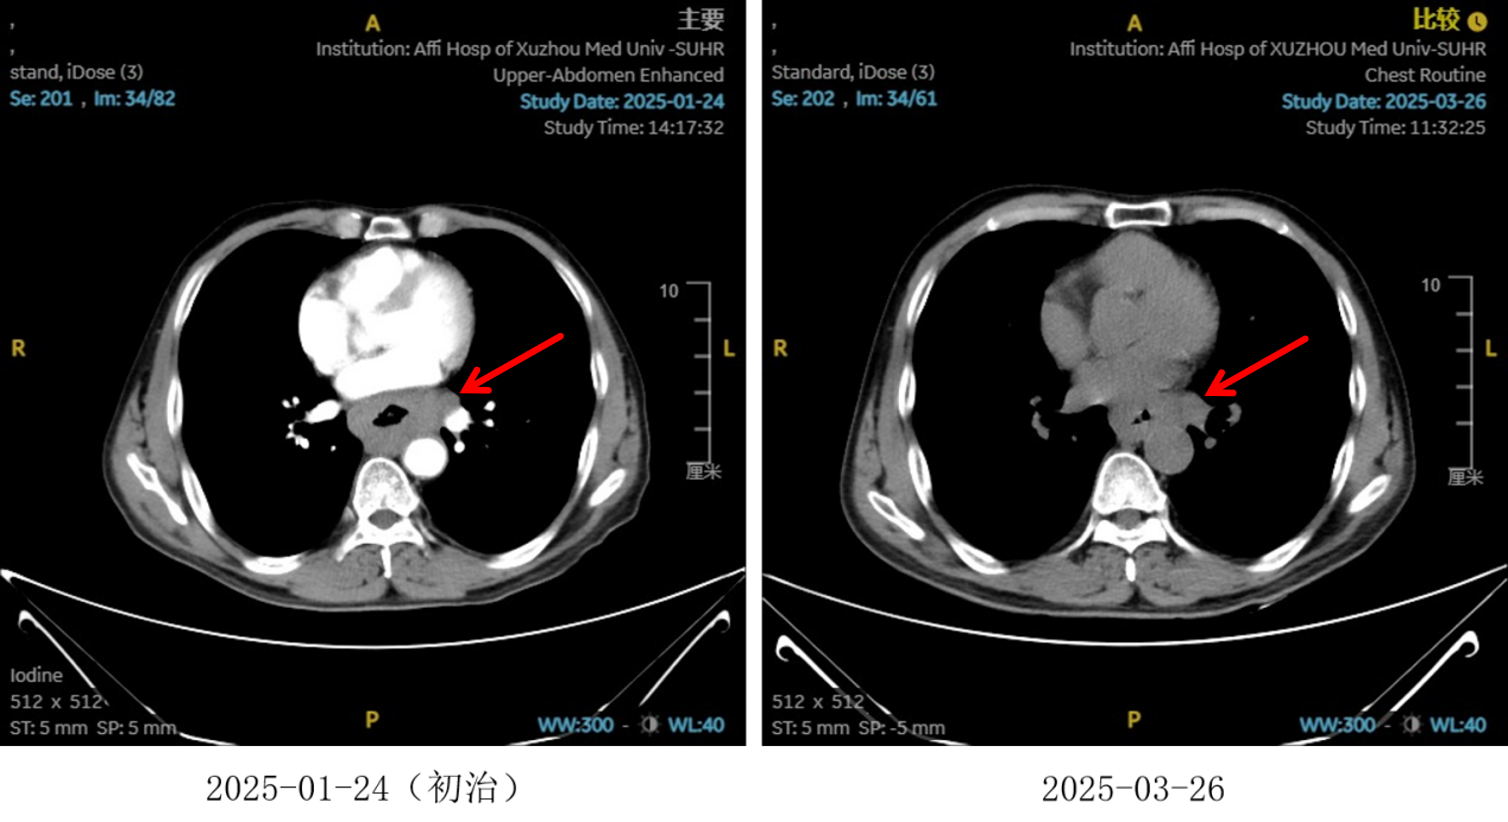

图2:2周期化疗联合抗血管治疗后食管癌病灶对比

图3:2 周期化疗联合抗血管治疗后淋巴结对比

图4:2周期治疗后影像学 [图左:“食管Ca化疗后”,食管胸中下段管壁增厚,较厚处管壁约15mm,边缘模糊,病灶局部与邻近大血管、气管壁分界不清。图右:纵隔内(3P、4、7)、左肺门及胃小弯旁示多发稍大、增大淋巴结影,部分融合,较大者大小约16mmx13mm。]

疗效评估

治疗2周期后,食管壁厚度由17mm降至15mm,淋巴结由18mm×15mm缩小至16mm×13mm;4周期后,食管壁进一步缩至12mm,淋巴结明显减少;6周期后,食管壁仅余10mm,纵隔内仅见小淋巴结影,疗效评估“接近CR”。